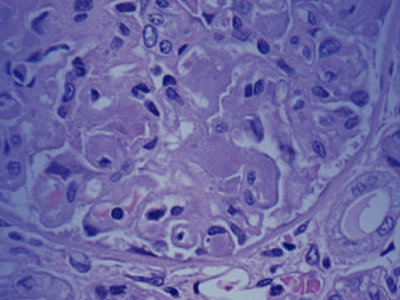

Besteht der Verdacht auf eine AL-Amyloidose, wird im Regelfall eine Gewebebiopsie durchgeführt.5 Dabei wird unter örtlicher Betäubung ein kleines Stück Gewebe aus dem Knochenmark, einem betroffenen Organ oder dem Bauchfett entnommen und auf Amyloid-Ablagerungen untersucht. Mit Hilfe dieser Methode kann nicht nur die Diagnose Amyloidose gestellt, sondern auch der Typ der Erkrankung identifiziert werden. Dies ist sehr wichtig, da es neben der AL-Amyloidose noch weitere Formen der Amyloidose gibt, wie beispielsweise die Transthyretin-Amyloidose, die teilweise ähnliche Symptome aufweisen, aber anders therapiert werden müssen.5

Biopsie Bei einer Biopsie werden kleine Gewebeteile aus dem Körper entnommen und im Labor z.B. unter dem Mirkoskop oder anderen Techniken auf Auffälligkeiten wie Amyloidfibrillen untersucht.